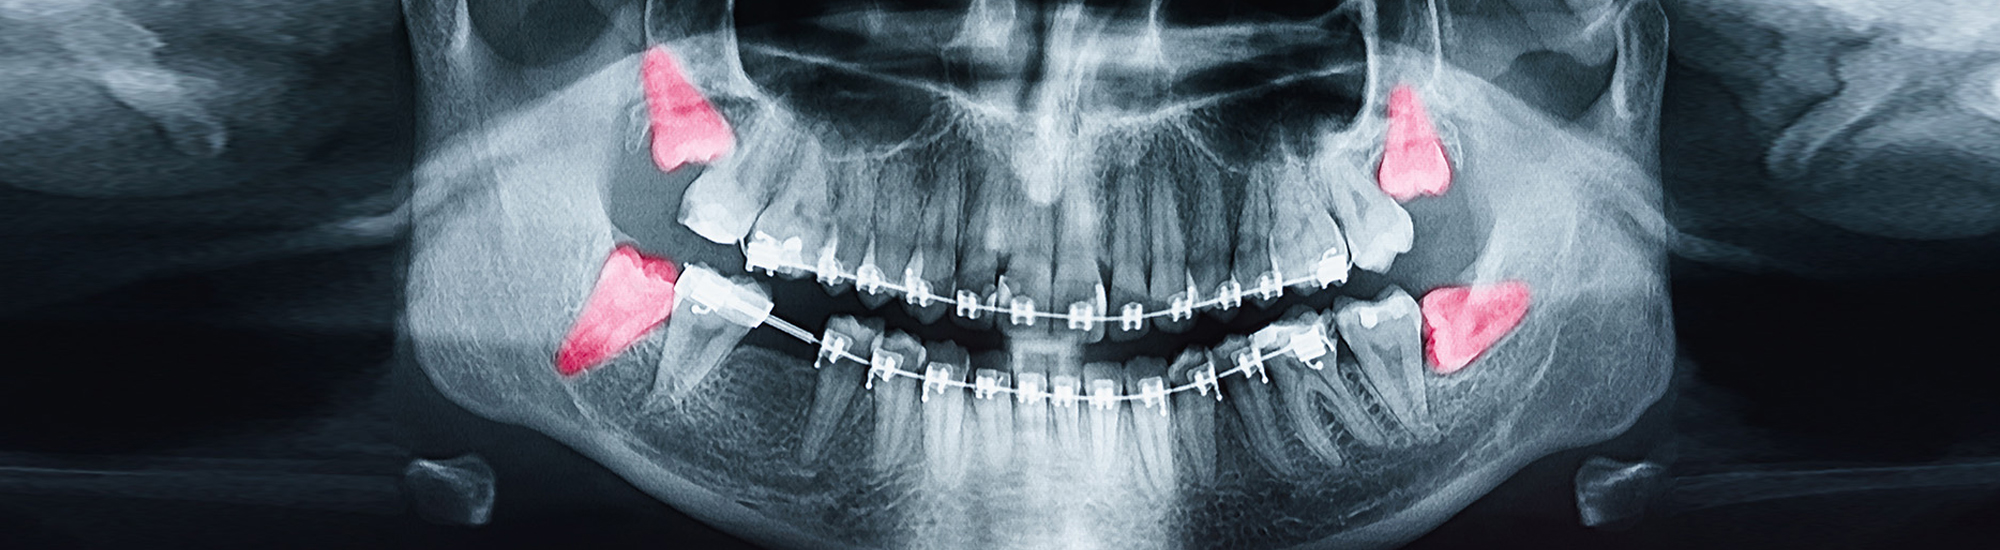

Wisdom teeth are the last set of molars to erupt and typically show up in the back corners of an adult's mouth between the ages of 16 and 25. This third set of teeth is not always successful and may press out other teeth when they emerge. They could also result in problems with your oral hygiene.

Since most people don't have enough room in their mouths for wisdom teeth or have other problems, extractions are common. The procedure is identical to that of other dental extractions. You will meet with your Brampton dentist at Bramdale Dental to go over the best course of action for your circumstances and why an extraction is necessary. The procedure will be carried out under sedation and a local anesthetic to minimize any discomfort.

If your tooth has completely erupted, our Brampton dental office may be able to do a simple extraction. For easier removal, the tooth might be divided into smaller pieces or extracted in one piece using forceps. However, since wisdom teeth are commonly affected, a surgical extraction is generally necessary. During wisdom teeth surgery, an incision is made in the gum line to remove any bone that covers the tooth before the tooth is actually removed. You could have stitches or sutures. To stop the bleeding, you will be given a piece of gauze to bite down on. During the first several days, some bleeding and edema are normal. An ice pack will help during this first stage.

If Bramdale Dental is concerned about the placement of your wisdom teeth, it could be necessary to have them pulled in order to avoid further problems. If you have any early worries regarding your wisdom teeth, get in touch with our Brampton dentist office right now.